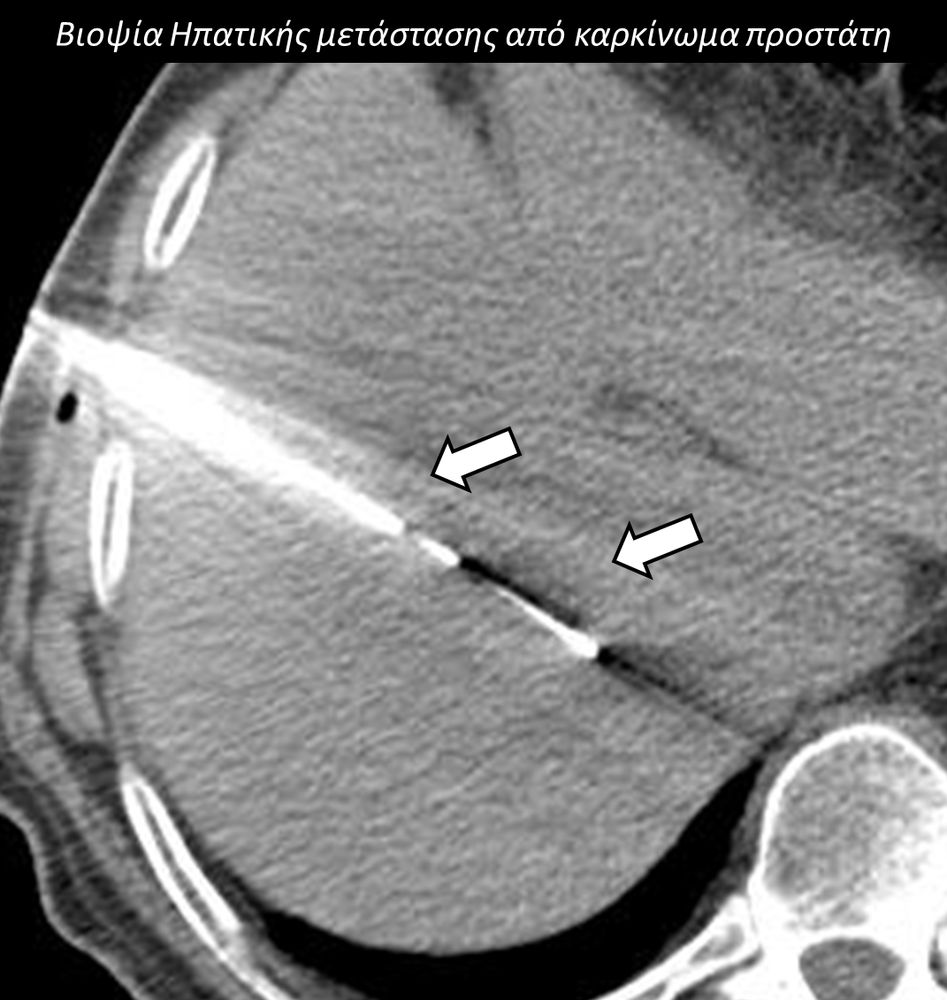

Η διαδερμική βιοψία είναι μία ελάχιστα επεμβατική μέθοδος λήψης υλικού από τον όγκο για κυτταρολογική και ιστολογική εξέταση, από εστιακές αλλοιώσεις του ήπατος, πνεύμονα, νεφρού κλπ. Συστήνεται από τον κλινικό ιατρό ανάλογα με το είδος και το μέγεθος της βλάβης και πραγματοποιείται με ασφάλεια από επεμβατικό ακτινολόγο με την καθοδήγηση αξονικού τομογράφου ή υπερήχων. Στη σύγχρονη ογκολογική θεραπεία όπου γίνεται προσπάθεια καταπολέμησης του καρκίνου σε μοριακό επίπεδο κρίνεται αναγκαία η ακριβής ιστολογική ταυτοποίηση του όγκου ώστε να εφαρμοσθεί εξατομικευμένη θεραπεία για το βέλτιστο αποτέλεσμα. Οι κατευθυνόμενες βιοψίες στοχευουν στο να παρέχουν στον κλινικό ογκολόγο το απαραίτο ιστοπαθολογικό υλικό που θα του επιτρέψει να εφαρμόσει την κατάλληλη θεραπεία για τον ογκολογικό ασθενή.